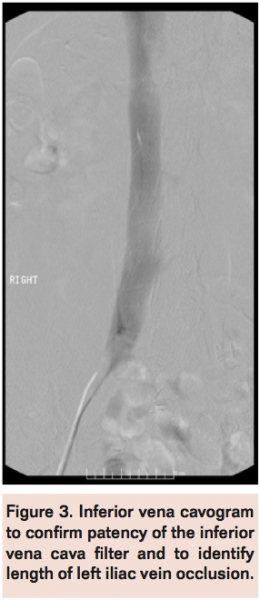

Selective bilateral venography was scheduled and the patient placed in prone position with ultrasound-guided bilateral popliteal vein access. A 7 Fr Ansel sheath (Cook Medical) was placed in the left popliteal vein and a 5 Fr Ansel sheath in the right popliteal vein. Selective venogram of the left popliteal vein confirmed occlusion of the left common femoral vein with extensive collateral network (Figure 2). Selective venogram of the right iliac vein demonstrated normal flow into the IVC (Figure 3) with normal appearance and positioning of the IVC, filter free of filling defects with brisk flow.